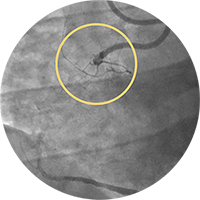

Внутристентовый рестеноз в левой передней нисходящей артерии: ко-регистрация данных с iFR и ВСУЗИ, лазерная атерэктомия, использование баллона с лекарственным покрытием и стентирование.

Хроническая тотальная окклюзия правой коронарной артерии. Изображение предоставил Крейг Томпсон, врач.